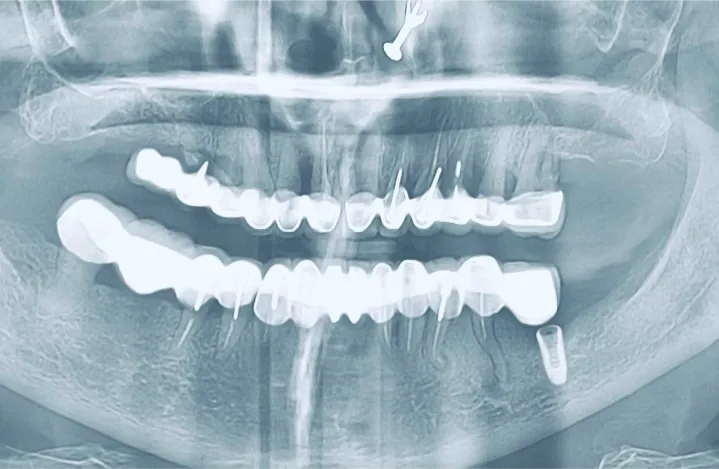

Accuracy, detail, and safety are at the forefront of our in-house CBCT and 3D dental imaging services. Single, full-arch or targeted scans provide precise, three-dimensional views of teeth, jawbone, and surrounding structures for effective diagnosis and treatment planning.

At iCube Dental, we use state-of-the-art CBCT and 3D imaging technology to ensure detailed, comfortable, and efficient scans. Our imaging services help dentists plan treatments with unmatched precision – enhancing outcomes for implants, orthodontics and complex restorations while keeping patient care safe and confident.

In-house CBCT and 3D imaging capture accurate, detailed views of your teeth, jaw, and gums, enabling precise diagnosis and treatment planning.

Advanced 3D scans reveal hidden dental issues, helping dentists plan treatments with accuracy and ensuring your smile and oral health are fully optimised.

Advanced in-house CBCT scans and 3D dental imaging at iCube Dental provide highly accurate, detailed views of teeth, jaws, and surrounding structures, supporting precise diagnosis and treatment planning.

Our state-of-the-art 3D imaging captures complete dental anatomy with minimal radiation exposure, allowing dentists to plan implants, orthodontics, and complex restorations with unmatched precision. In-house CBCT and 3D scans at iCube Dental enhance patient safety, optimize treatment outcomes, and provide a comprehensive view of oral health for confident, effective care.